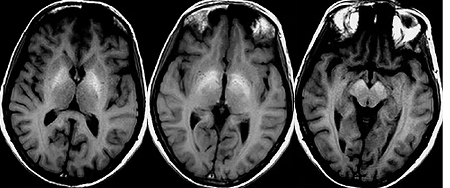

影像资料:

T1

T2

T2FLAIR

DWI

MRI 影像描述:T1W1 可见双侧苍白球对称高信号,T2、T2FLAIR、DWI 相应部位均未见确切异常信号。